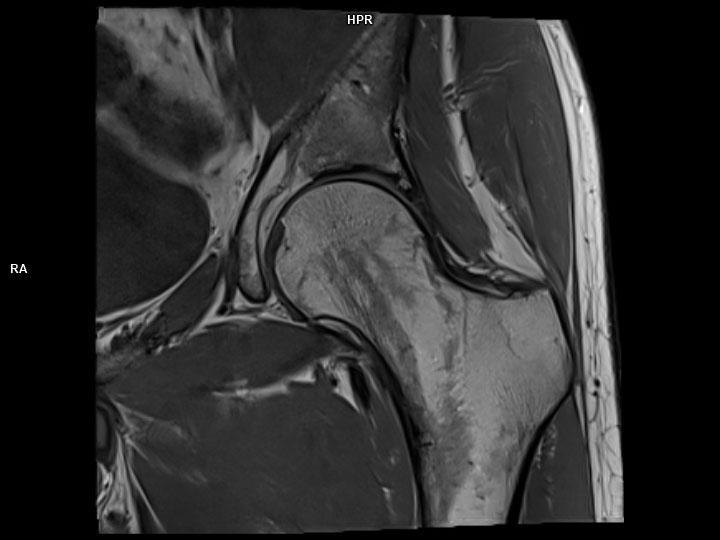

Coronal T1 TSE-MAGNETOM Lumina

Coronal T1 TSE-MAGNETOM Lumina/Coil-Ultraflex 18 Large/Resolution-320/Scan Time-3:36/Aceleration-p2